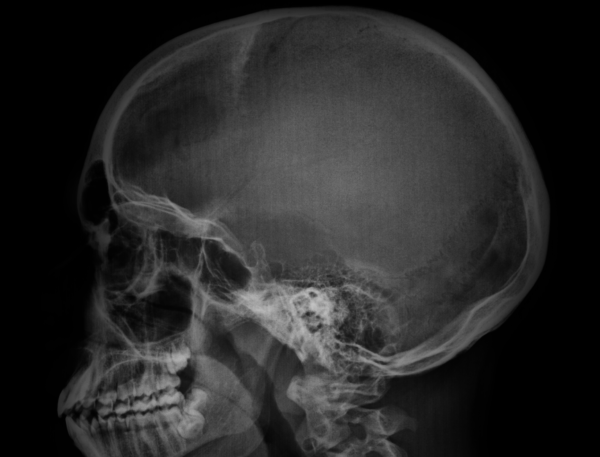

Paciente de seis anos, em investigação de lesão lítica na calota craniana. Realizou radiografia de crânio em Ap e perfil para melhor avaliação.

Quais suspeita diagnóstica e a melhor descrição das imagens acima?

ALesão lítica, bem definida, com halo de esclerose, na região frontal esquerda – granuloma eosinofílico.

BLesão lítica, bem definida, com halo de esclerose, na região frontal direita – osteomielite aguda

CLesão lítica, com sinais de agressividade, alargando a sutura coronal esquerda – displasia fibrosa

DLesão blástica, mal definida, na região frontal esquerda- granuloma eosinofílico